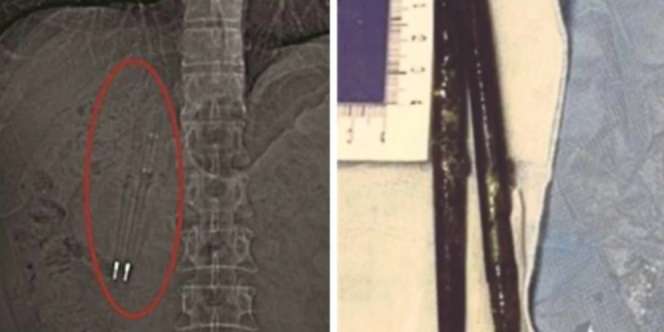

Dilansir dari Harian Metro, Jumat 12 Mei 2017, harian People’s Daily menyebutkan seorang pria bernama Wang menjalani pemeriksaaan fisik pada Februari 2017. Saat melakukan CT Scan, dokter menemukan ada benda aneh yang berada di perut dia.

Lalu, pada Mei 2017, Wang pun menjalani operasi pada 4 Mei 2017. Ketika operasi berlangsung, dokter menemukan dua benda aneh di dalam perutnya, yaitu dua buah pulpen.

Pulpen ini terjebak di dalam perut pria berusia 50 tahun selama 36 tahun. Ajaibnya, pulpen sepanjang 11,64 cm ini tidak rusak sedikit pun.